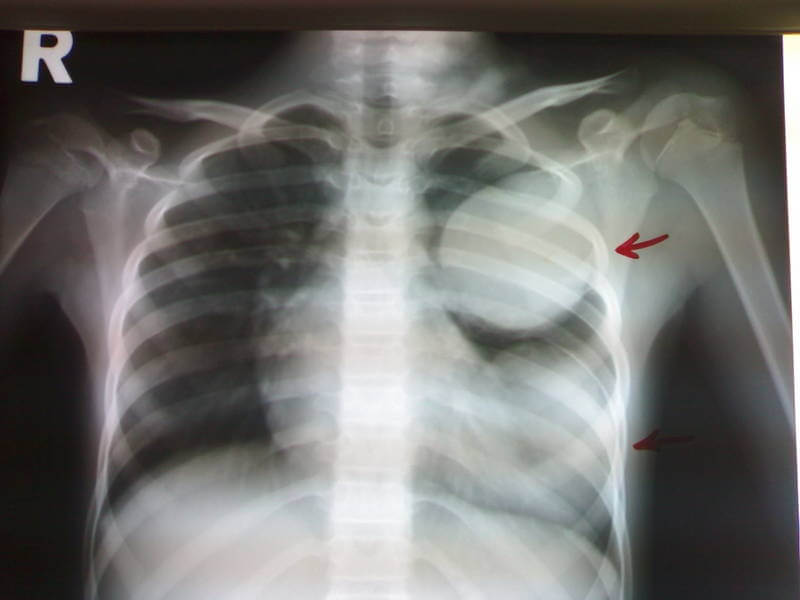

Эхинококкоз легких

Более чем в 20% всех зарегистрированных случаев эхинококкоза поражаются легкие. Клиническую картину болезни можно разбить на две стадии. Первая — это стадия нелопнувшей эхинококковой кисты. На этом этапе заболевшие жалуются на боли в грудной клетке, сначала периодические, а затем постоянные. Также возникают одышка, кашель сначала сухой, а затем — влажный с отделением слизисто-гнойной мокроты, кровохаркание. Все эти симптомы обусловлены сдавливанием растущей кистой тканей легкого, бронхов, сосудов. Пузырь может нагноиться. В таком случае формируется абсцесс легкого.

Вторая стадия — это период вскрывающейся кисты. При прорыве кисты в бронх возникают сильнейший кашель, удушье, цианоз кожи. В мокроте иногда можно обнаружить примеси крови, обрывки оболочки кисты в виде пленок. Эти симптомы сохраняются несколько дней и отягощаются тяжелой аллергией. При прорыве кистозного образования в плевральную полость возникают сильнейшая боль в грудной клетке, выраженный подъем температуры тела, озноб. Если разрывается жизнеспособная киста со сколексами эхинококка, тогда паразиты распространяются вокруг с развитием вторичного эхинококкоза. Клинически вторичный эхинококкоз проявляется спустя пару лет.

- Инструментальные методы (УЗИ, КТ, МРТ, рентгенография) — определяются округлые образования (кисты) в ткани пораженного органа.